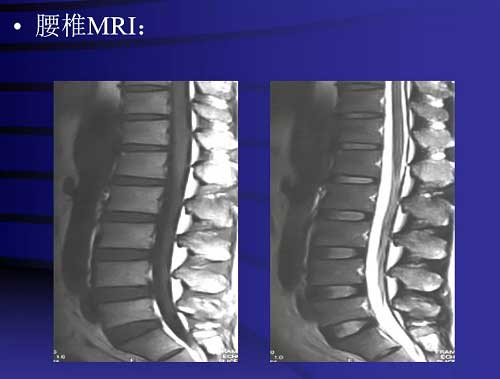

演讲题目:疼痛影像培训(DR、CT、MRI)